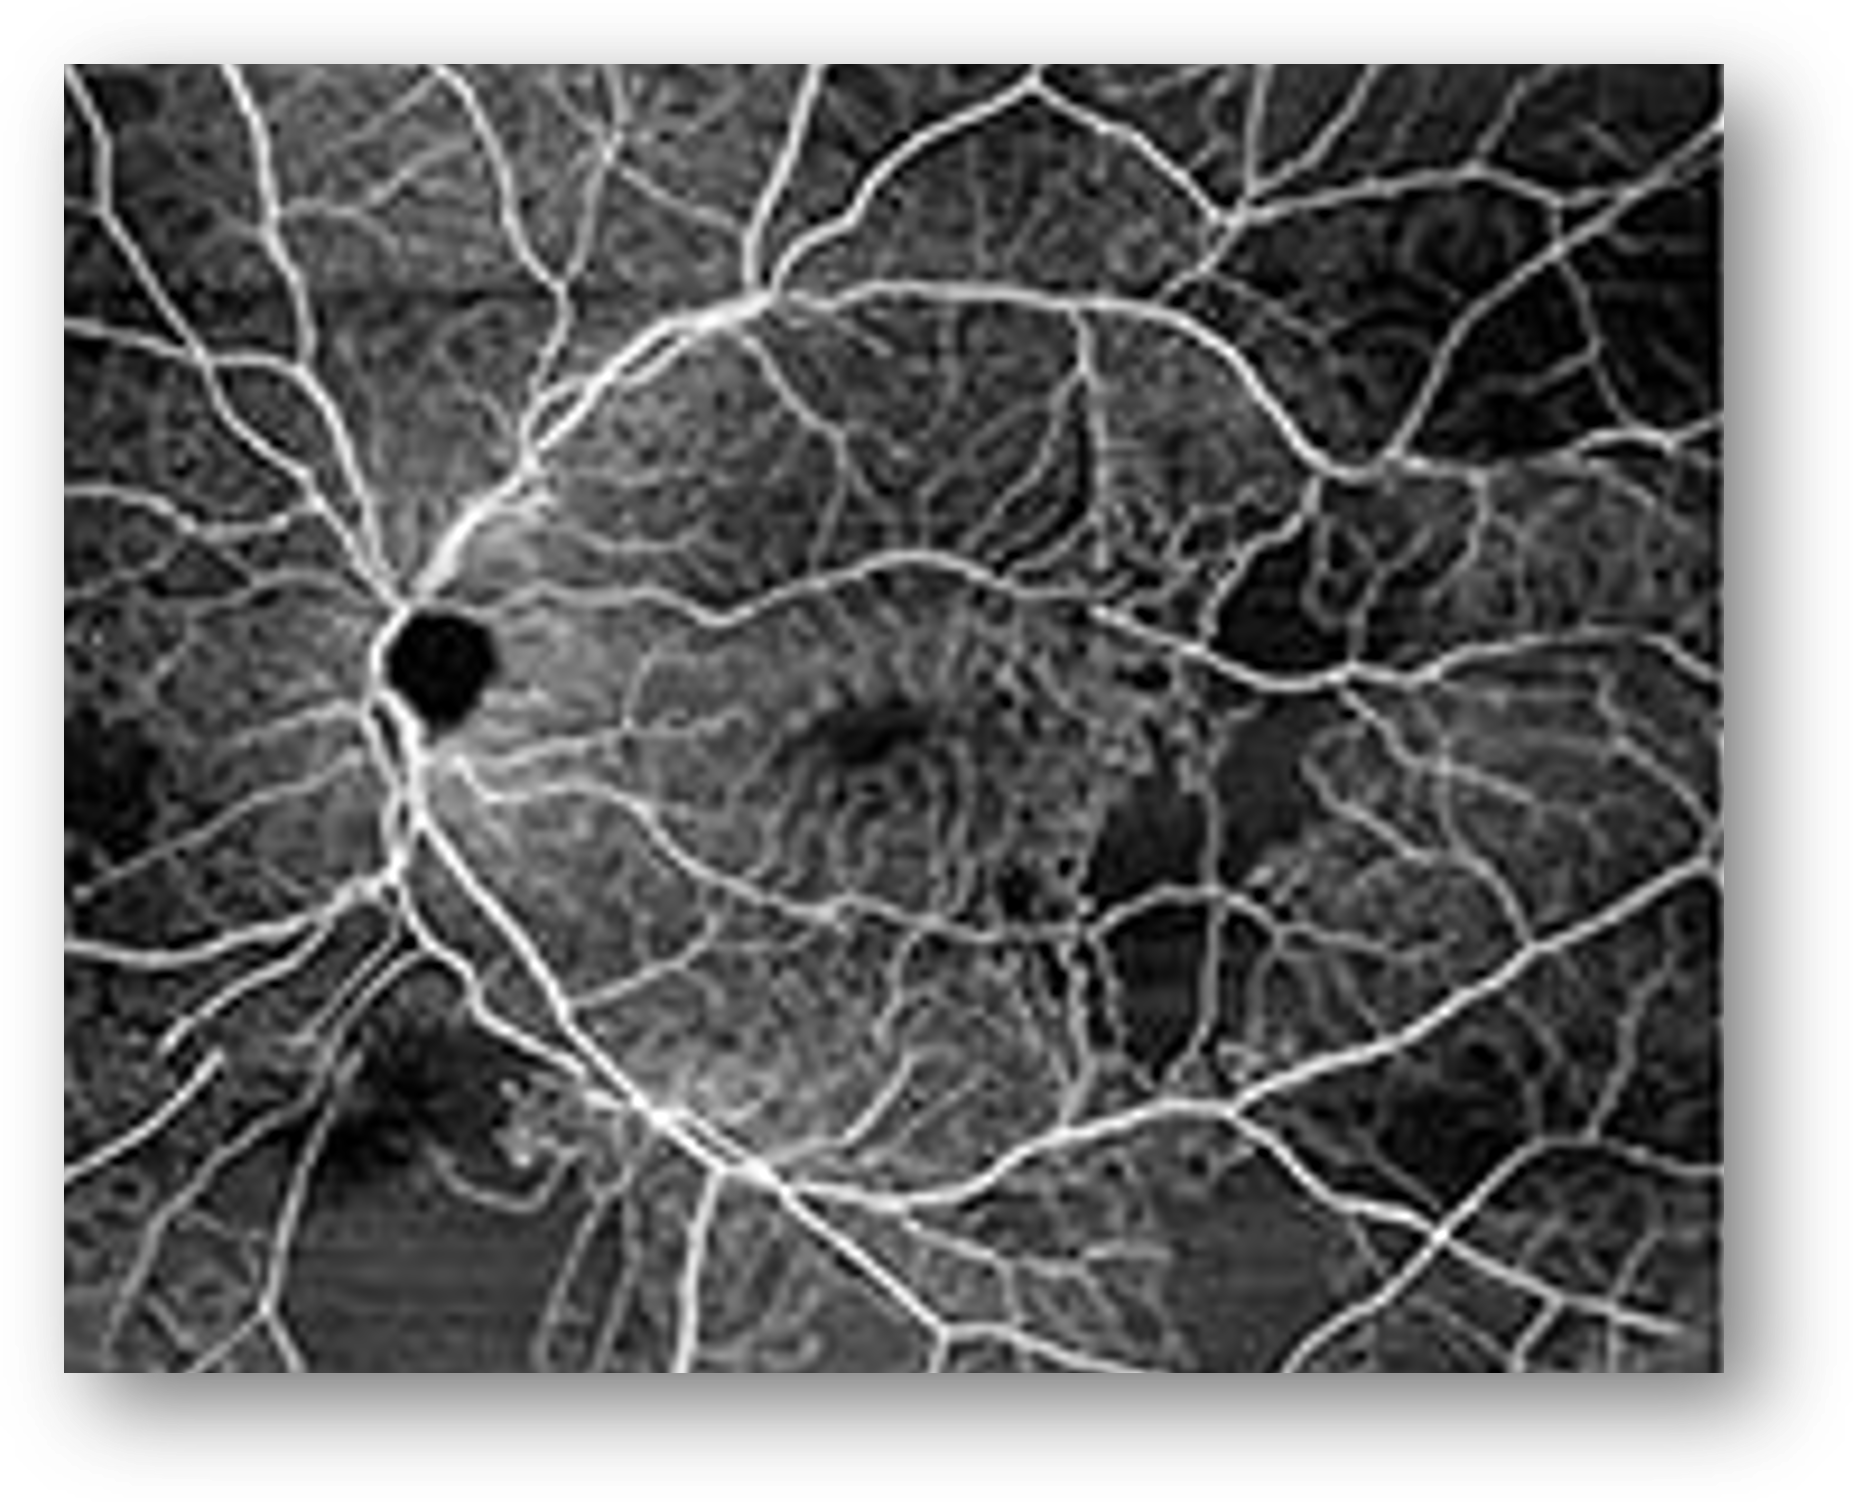

At the four-month follow-up, we discovered rapidly worsening DR with incident optic nerve neovascularization in the left eye. In fact, the difference in four month’s time is remarkable when you look at the photos side by side (Figure 5). I diagnosed the patient with PDR and referred him to a retinal specialist.

Figure 5: Fundus Photography